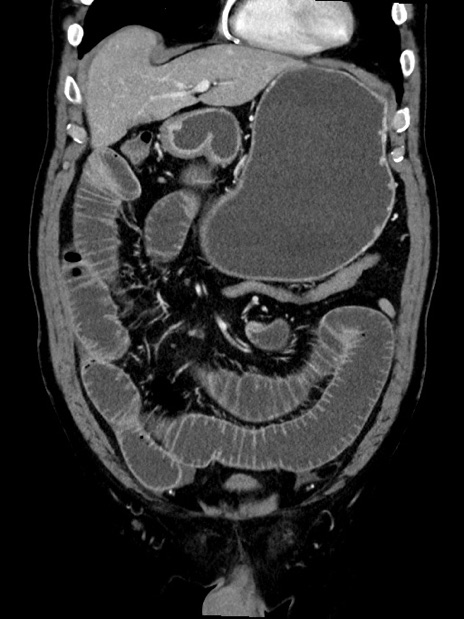

症例35(冠状断像)

【症例】70歳代 男性

【主訴】腹部膨満、嘔吐

【現病歴】昨日より腹部膨満感出現。本日増悪し、仙痛出現。嘔吐あり、受診。

【既往歴】糖尿病、胆摘後

【身体所見】BP 149/80mmHg、HR 74/min、BT 35.9℃、腹部:膨満、軟、圧痛なし。腸雑音減弱あり。上腹部正中切開瘢痕あり。

【データ】WBC 13500、CRP 1.72